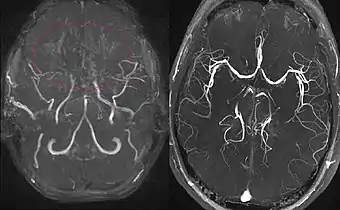

En réaction à cette occlusion se développe un réseau vasculaire anormal au niveau de la base du crâne, dont l’aspect angiographique en « nuage de fumée » (en japonais : もやもや, moyamoya) a donné son nom à la maladie.

En 1968 et 1969, Kudo, Nishimoto et Takeuchi, ainsi que Suzuki et Takaku, ont publié leurs études dans la littérature anglaise, ce qui a grandement contribué à la reconnaissance de la maladie de moyamoya dans le monde entier[1]. Ces auteurs ont également décrit les 6 étapes de progression angiographique, du stade 1 (rétrécissement de l'artère carotide) au stade 6 lorsque se développe un réseau vasculaire anormal au niveau de la base du crâne avec son l’aspect angiographique en « nuage de fumée ».

(à droite) Patient en bonne santé, pour comparaison.

L'IRM cérébrale constitue l'examen de choix chez l'enfant, permettant de faire le diagnostic de l'accident vasculaire cérébral et d'en suspecter le mécanisme[9]. l'examen doit être complété par une angiographie cérébrale au cours d'un scanner.